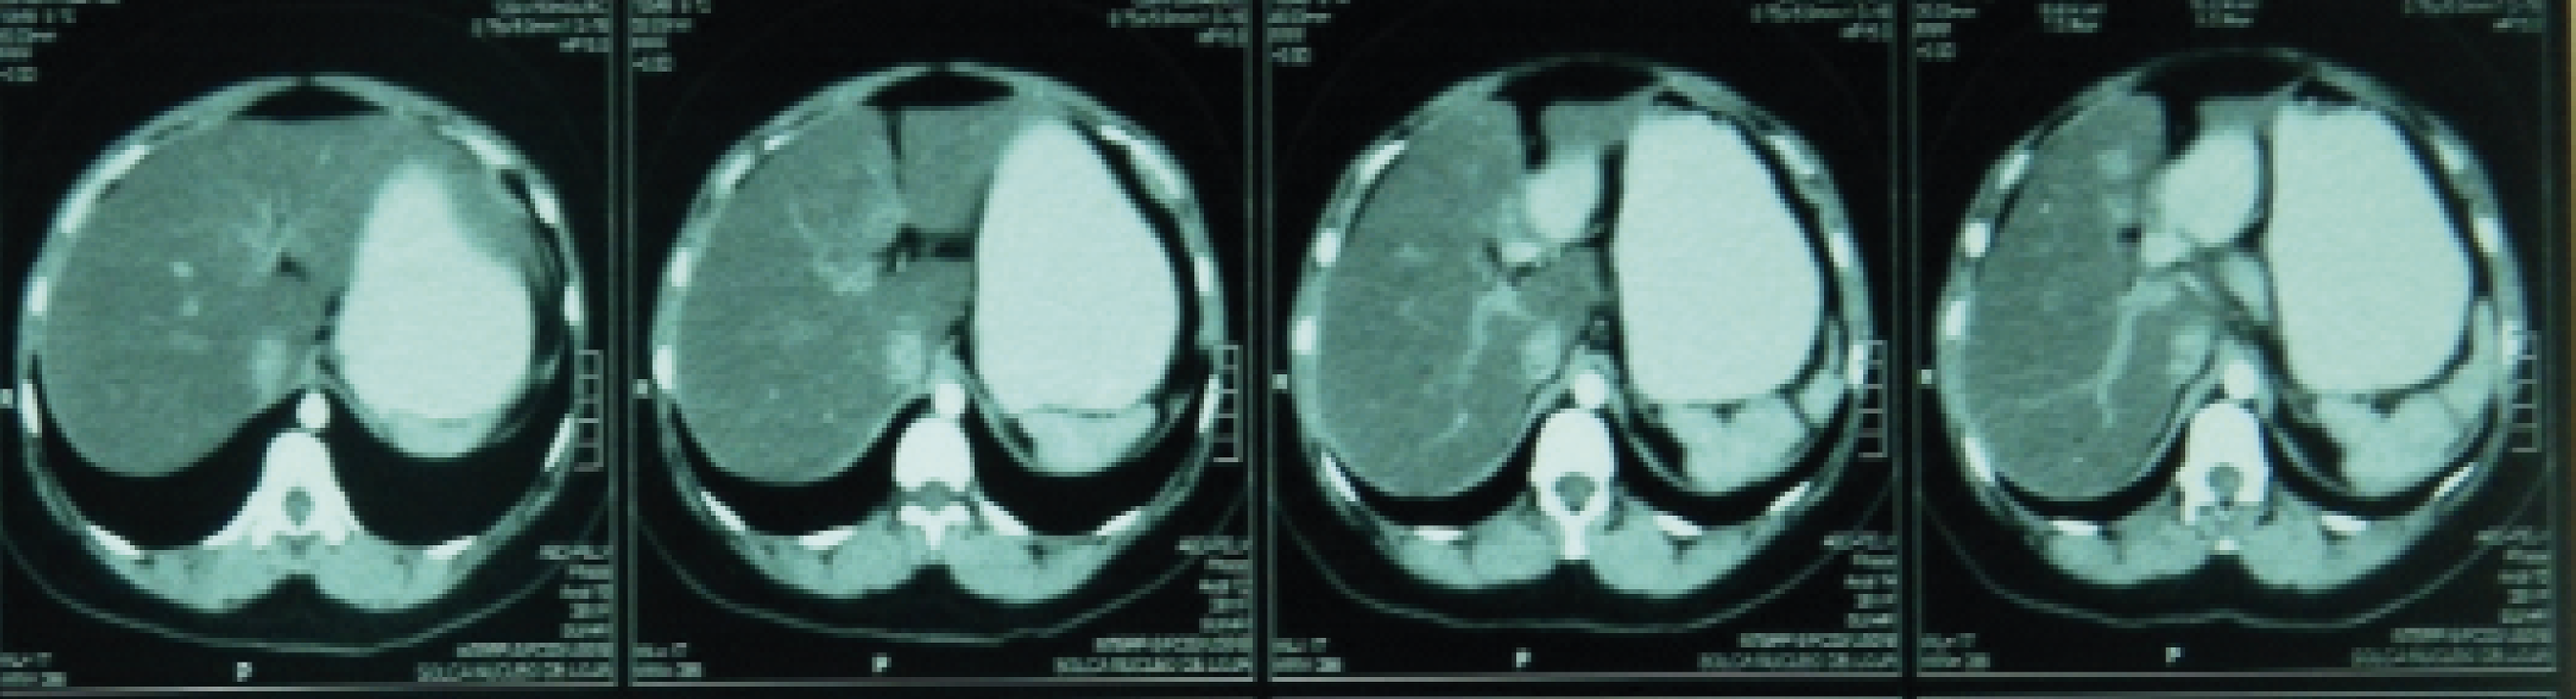

La evaluación por imagen del 12 de mayo de 2014 muestra TAC de tórax negativa para actividad tumoral y TAC de abdomen con resolución completa del nódulo del parénquima hepático.

Figura 2. Se aprecia el hígado sano, sin la presencia del nódulo antes descrito.